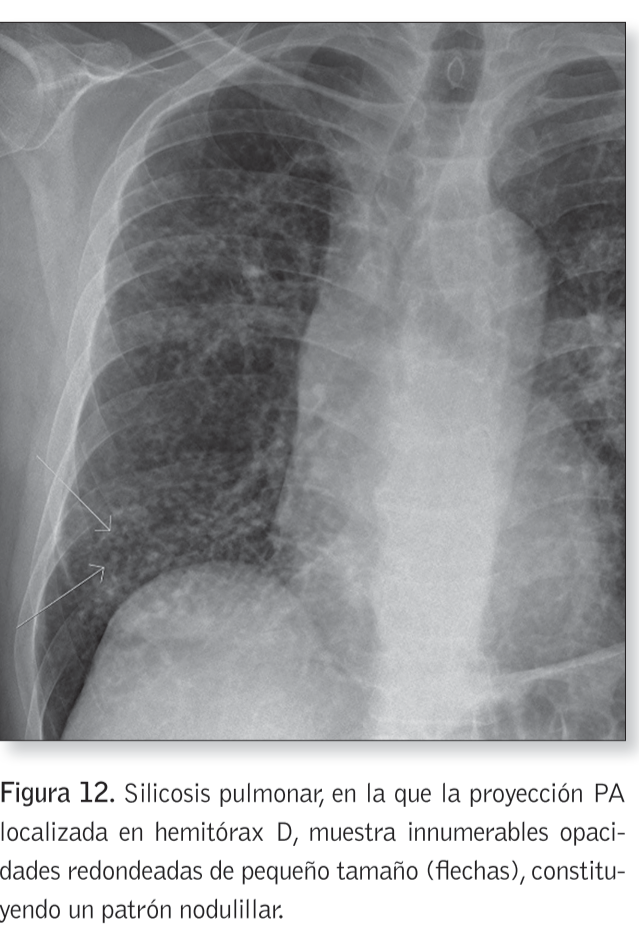

3) Patrón nodulillar o modular

Patrón nodulillar o nodular